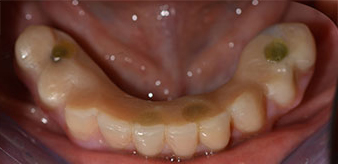

After removal of the residual dentition in the mandible, the alveolar crest was exposed from 37 to 47.

The mental foramen was first identified as a limiting anatomical structure and then the cortical bone of the crest was smoothed with the straight handpiece and a large rose-head bur (Fig. 4).